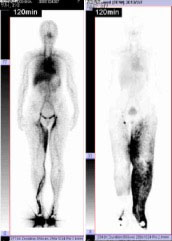

リンパ管静脈吻合の術前検査としてリンパ管シンチグラフィーという検査を行います。リンパ管シンチグラフィーでは下肢または上肢など浮腫んだ部位の皮下に造影剤(ラジオアイソトープ)を注射して行う放射線検査です(下図)。造影剤を注射後の15分と120分位撮影を行うことで、(1)リンパ浮腫の確定診断、(2)リンパ浮腫の部位の同定、(3)リンパ管の機能評価を行います。(3)のリンパ管の機能評価は手術の効果を予測する上でとても重要な項目です。リンパ管静脈吻合では静脈とリンパ管を顕微鏡下に吻合しますが、リンパ管の平滑筋機能が保たれていると、リンパ管が静脈へリンパを効率的に送り出すため、手術の効果が得られるためです4。

左:右大腿にリンパの貯留がある。

右:左下肢全体にリンパの貯留がある。